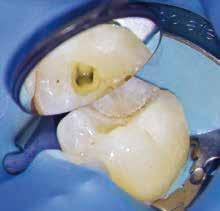

Egy 38 éves nőbeteg a korábban kezelt jobb felső második kisőrlőfogából (1.5) kiinduló mérsékelt fájdalom miatt jelentkezett rendelésünkön. A kórtörténetében jelen panasza szempontjából releváns információ nem szerepelt. A beteg a klinikai vizsgálat során vertikális kopogtatásra enyhe érzékenységet jelzett. A kérdéses fog körül mérhető szondázási mélység és a fogmobilitás fiziológiás volt. Periapicalis röntgenfelvételen egy, a fog gyökércsúcsán túl presszálódott betört gyökérkezelő műszerből származó eszközfragmentumot láttunk (2. a. ábra). A preoperatív CBCT-felvétel a buccalis csontlemez épségét igazolta (2. b-c. ábra). A fog revíziója öt hónappal korábban történt. A már előzőleg gyökérkezelt, gyökértömött, majd revideált 1.5-ös fog esetében a diagnózisunk periodontitis periapicalis symptomatica volt. A periapikális elváltozás kezelése érdekében navigált endodonciai mikrosebészeti beavatkozást végeztünk.

A felső állcsontról intraorális szkent (TRIOS) készítettünk, és az ezáltal kapott STL fájlt (2. d. ábra) a CBCT-felvétel során nyert DICOM fájlokkal a Zirkonzahn.Implant-Planner (Zirkonzahn) szoftverben egyesítettük. A sebészi sablont ebben a programban megterveztük, majd a Meshmixer (Autodesk) szoftver se-

gítségével tovább módosítottuk. Az így kapott sebészi sablon egyértelműen meghatározta a periapikális terület eléréséhez szükséges csontablak határait (2. e-f. ábra) Helyi érzéstelenítést követően teljes vastagságú mucoperiostealis lebenyt képeztünk, majd a buccalis csont feltárását követően (2. g. ábra) a sablon segítségével bejelöltük a preparálandó csontablak határait (2. h. ábra). A csontablak kialakítása során Piezotome CUBE LED kézi-darabot alkalmaztunk, majd a leemelését követően a betört eszközt megkerestük (2. i. ábra) és eltávolítottuk (2. j. ábra). A rezekciót ultrahangos megmunkáló fejekkel (ACTEON) végeztük, majd retrográd preparáció következett.

A retrográd gyökértömés elkészítése során TotalFill BC RRM Fast Set Putty-t (FKG) használtunk (2. k. ábra). A lebeny széleit 5/0-s Prolene varratokkal egyesítettük (2. l. ábra). A varratok a műtétet követően 72 órával kerültek eltávolításra. A beteg két évvel később kontrollröntgen készítése céljából érkezett rendelőnkbe. A vizsgálat során a fog tünetmentesnek és funkcióképesnek bizonyult (2. m. ábra).